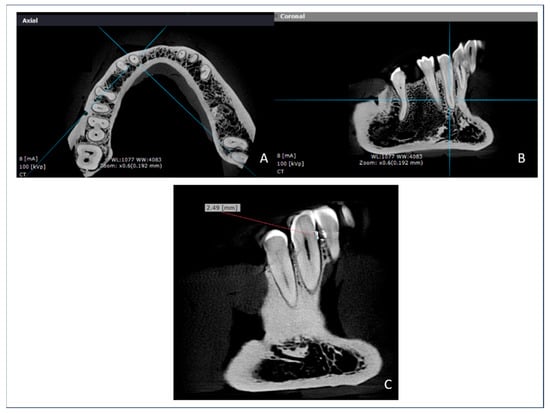

All image analyses were conducted by a single trained examiner and calibrated for the evaluation protocol. Paracoronal slices were generated using OnDemand3D software (Cybermed, Tustin, CA, USA), with a 2× sharpening filter and standard window settings (WL = 1077, WW = 4083). Although CBCT provides three-dimensional imaging, this study was limited to two-dimensional linear measurements obtained from paracoronal slices. Although this method is widely used and offers high reproducibility, it does not fully leverage the volumetric capabilities of CBCT technology. Future research should explore the implementation of 3D volumetric segmentation and analysis techniques, which may enable a more comprehensive evaluation of periodontal bone morphology and spatial distribution.

In the software’s Dental module, each tooth was centered in the axial plane, and the slice orientation was adjusted to obtain optimal paracoronal views. Linear measurements were performed from the radiopaque CEJ marker to the alveolar crest using the built-in measurement tool. Each measurement was performed in triplicate and recorded in Microsoft Excel. Including the in situ measurements, a total of 642 data points were collected.

Figure 2 presents representative screenshots from the OnDemand3D software, illustrating the image processing workflow used in this study. The axial view (Panel A) was used to define the orientation for paracoronal reformatting. Panel B shows a paracoronal slice of the region of interest, while Panel C demonstrates the linear measurement from the radiopaque CEJ marker to the alveolar crest. All measurements were performed in triplicate by a calibrated examiner using standardized window settings and image enhancement filters.